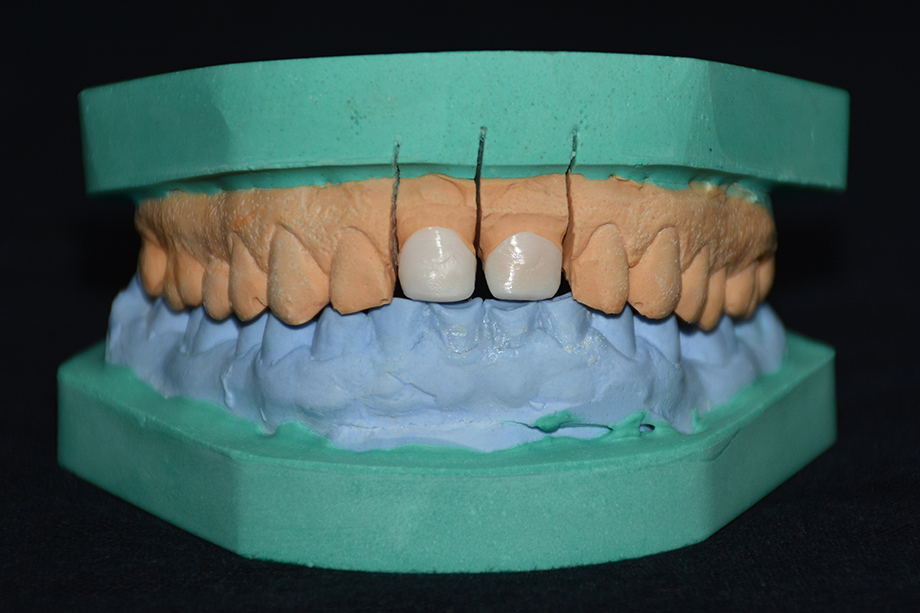

Patientenfall: Restauration zweier Inzisiven mit Zirkoniumdioxid in Kombination mit VITAVM®9

VITA VM 9 ist eine natürliche Feldspat-Verblendkeramik mit Feinstruktur für Zirkondioxidgerüste, VITABLOCS Mark II und PM 9.